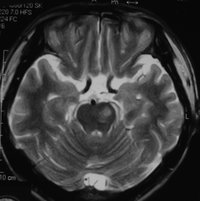

腦幹梗塞腦幹梗塞:椎基底動脈及其分支有粥樣硬化,或動脈栓塞、痙攣、炎症導致管腔狹窄、缺血而引起的循環障礙。最常見於腦橋。主要病理改變是腦軟化。多見於中老年,常常有高血壓動脈硬化或有基底動脈供血不足病史。發病較急,主要表現偏癱或四肢癱,吞咽及發音困難,高熱,意識障礙(昏迷、緘默症等)。由於受累血管不同引起不同部位的梗塞,表現各種交叉性癱瘓。腦梗塞俗稱“中風”或“腦卒中”。“中風”分為“出血性中風”和“缺血性中風”,“缺血性中風”即腦梗塞,它包括腦血栓形成、腦栓塞等,腦梗塞在所有中風中占70%至80%,近幾年來明顯增多,且向年輕化發展。有的病人僅僅27歲,但大多數為45歲以上的中老年。 腦梗塞的主要病理變化是在腦動脈硬化的基礎上,血管內形成血栓,阻塞了血流,造成腦組織的缺血、缺氧和壞死,使病人出現偏癱、失語、偏側肢體麻木、走路不穩、大小便失禁、精神錯亂、痴呆、甚至成為植物人,部分腦幹梗塞和大面積腦梗塞可致命。早期治療、早期干預可以改善病人預後,減輕和減少致殘。因為大量臨床資料表明,發病後6小時內經過有效的溶栓治療,可以使血栓溶解血管再通、使腦梗塞痊癒率達到70%至80%,個別資料報導可達近90%,不留有任何後遺症。 [治法]:益氣和血,通絡降脂,活血,化痰 [藥方]:黃芪30 丹參20 廣地龍12 川芎15 赤芍12 當歸15膽南星10 白芍12 石菖蒲15 葛根20 水蛭10 山楂18 首烏20 [化裁]:1.肝陽偏亢者,加天麻10 鉤藤12 2.血壓偏高者,加夏枯草18 石決明20 3.痰多者,加天竺黃12 4.大便乾結者,加大黃10 5.出現面癱者,加全蠍10 附子8 6.失語者,加遠志12 鬱金12 7.上肢不遂者,加桑枝15 薑黃12 8.下肢不遂者,加桑寄生15 杜仲15